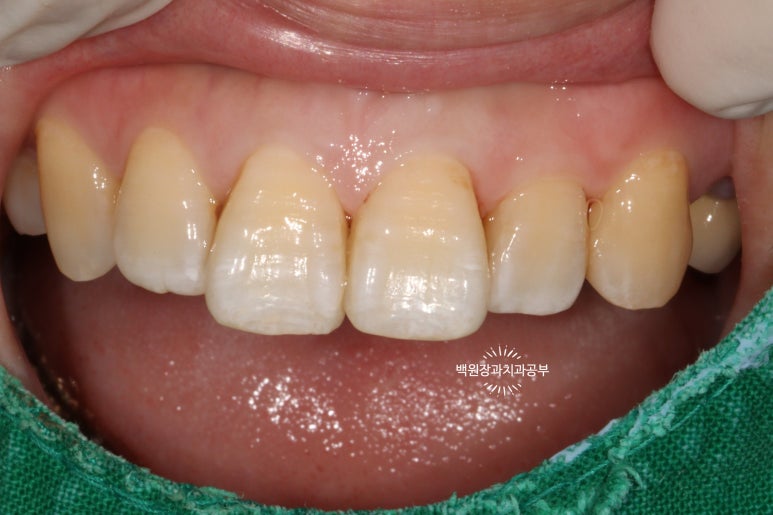

서론이 길었네요. 60대 여자 환자분이시고 위 앞니 사이사이에 있는 인접면 충치 치료차 내원하셨습니다.

정면을 보면, 치아 사이사이에 있는 충치가 얼핏 보이실거에요!

하얀것은 치아고 까만것은 충치라는걸 유치원생도 다 구분할 수 있을거에요. ㅎㅎㅎ

위턱 앞니의 사이사이마다 인접면 충치가 보이네요...

더 확실하게 보여드리기 위해 고개를 살짝 돌려서 보면..

고개를 돌려서 보면 인접면 충치를 더 잘 확인하실 수 있습니다!

집에서 확인해 보실 때도 고개를 돌려서 보셨었겠죠?